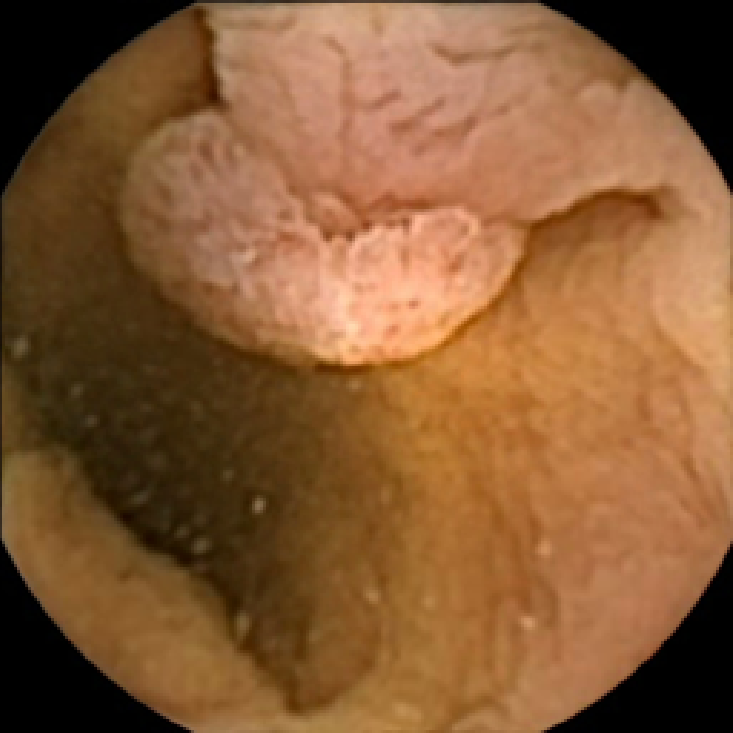

The lower bound filters out the frames with too little texture content that are unlikely to contain any polyps due to most polyps having a textured surface. The upper bound allows us to discard the frames polluted with trash and bubbles, since even if they contain polyps, they are likely to be obscured. This is illustrated in Figure 2, where we display two normal frames with low and high values of and a polyp frame with a medium value of . As expected, the first normal frame containing flat mucosa has little texture content. The second normal frame polluted with bubbles has strong texture content in the bubbles area, which is especially pronounced in the plot of . Finally, the polyp frame has moderately textured polyp area, which can also be easily observed from that has the strongest feature in that region.

In Figure 5 we show the circles of radius corresponding to the features that were correctly classified as polyps by (29). We observe that the classifier was able to identify the polyps of a variety of shapes even in the presence of small amounts of trash liquid (first row) or when the polyps are located next to mucosal folds (rows two to four in column (c)).